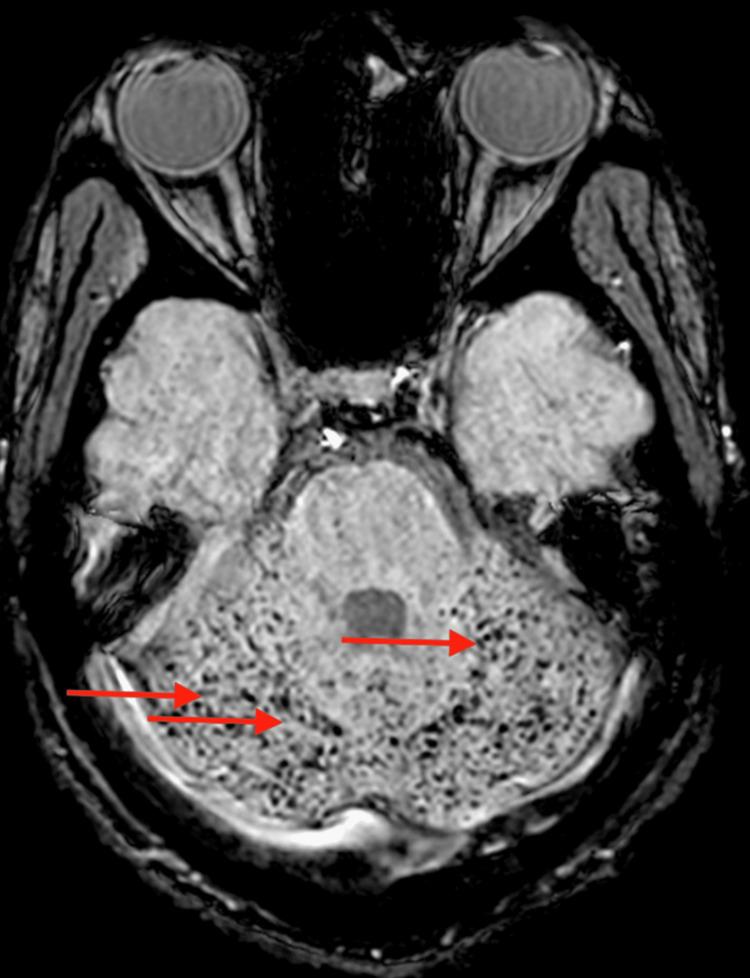

Sickle cell disease is one of the most common inherited hemoglobinopathies diagnosed in the United States. Patients often present with severe anemia, pain crises, infections, and vaso-occlusive phenomena. Complications of these disorders can lead to significant debilitating morbidity and mortality. Fat embolism syndrome (FES) is a rare and devastating complication of sickle cell disease. It usually presents with a rapidly deteriorating clinical course, and the prognosis is dismal. We report a case of FES in a 19-year-old African American male with a history of sickle cell disease who presented with tonic-clonic seizures and was found to have multi-organ failure. FES was diagnosed 20 days from a presentation based on blood cytopenias and magnetic resonance imaging findings that were obscured at the initial presentation. We describe in this report, the patient's course from presentation until diagnosis and resolution. Our case is peculiar as the patient had a very good outcome without the need for red blood cell (RBC) exchange; instead, supportive treatment and simple RBC transfusions were enough to change the clinical course of this almost fatal syndrome.

镰状细胞病是美国诊断出的最常见的遗传性血红蛋白病之一。患者常出现严重贫血、疼痛危象、感染和血管阻塞现象。这些病症的并发症可导致严重的致残性发病和死亡。脂肪栓塞综合征(FES)是镰状细胞病一种罕见且严重的并发症。它通常表现为临床病程迅速恶化,预后不佳。我们报告一例19岁非裔美国男性镰状细胞病患者发生FES的病例,该患者出现强直阵挛性癫痫发作,被发现有多器官功能衰竭。根据血细胞减少和磁共振成像结果,在出现症状20天后诊断出FES,这些结果在初次就诊时并不明确。我们在本报告中描述了患者从就诊到诊断及康复的过程。我们的病例很特殊,因为患者无需进行红细胞置换就取得了很好的治疗效果;相反,支持性治疗和单纯的红细胞输血就足以改变这种几乎致命综合征的临床病程。